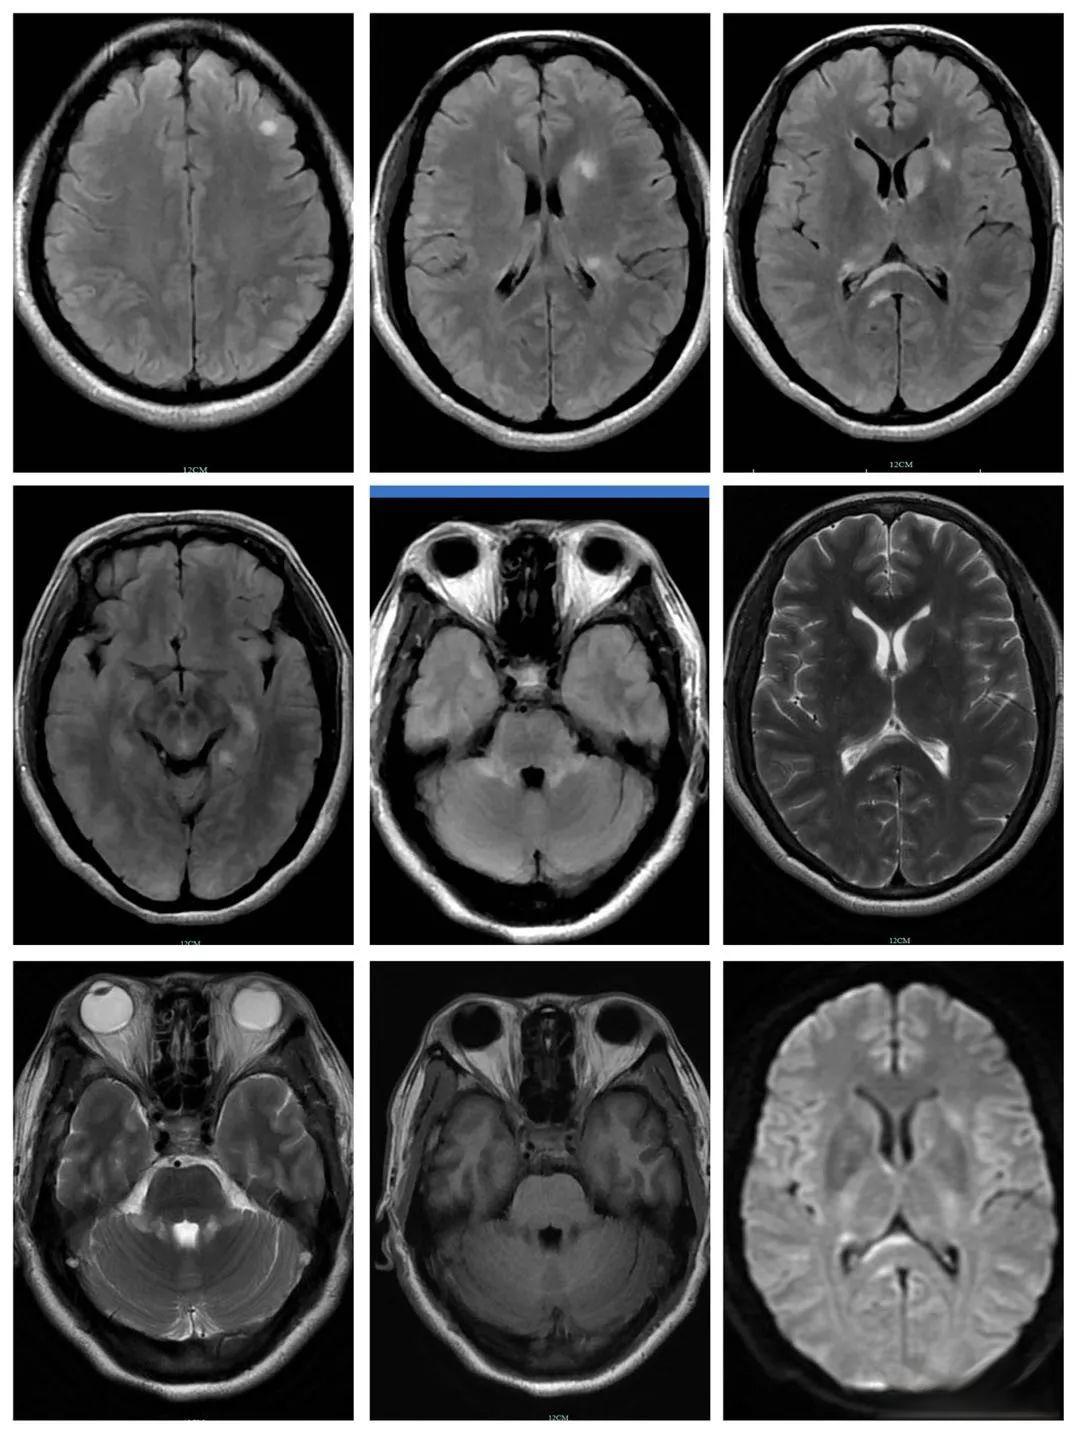

一名42岁的女性患者因“口干、眼干10年,右下肢无力10天”入院。 她10年前开始出现口干、眼干症状,后被诊断为干燥综合征(SS)和肾小管酸中毒。 然而,近来她出现了右下肢无力、左下肢麻木等症状,颈椎胸椎MRI显示颈5 7、胸2 6椎体水平髓内有长T1长T2信号影,增强呈斑片状强化。颅脑MRI也发现双侧额顶叶白质区有多发斑块样、斑点状等T1稍长T2信号。经过一系列检查,她最终被诊断为干燥综合征合并髓鞘少突胶质细胞糖蛋白(MOG)抗体相关性脑脊髓炎。